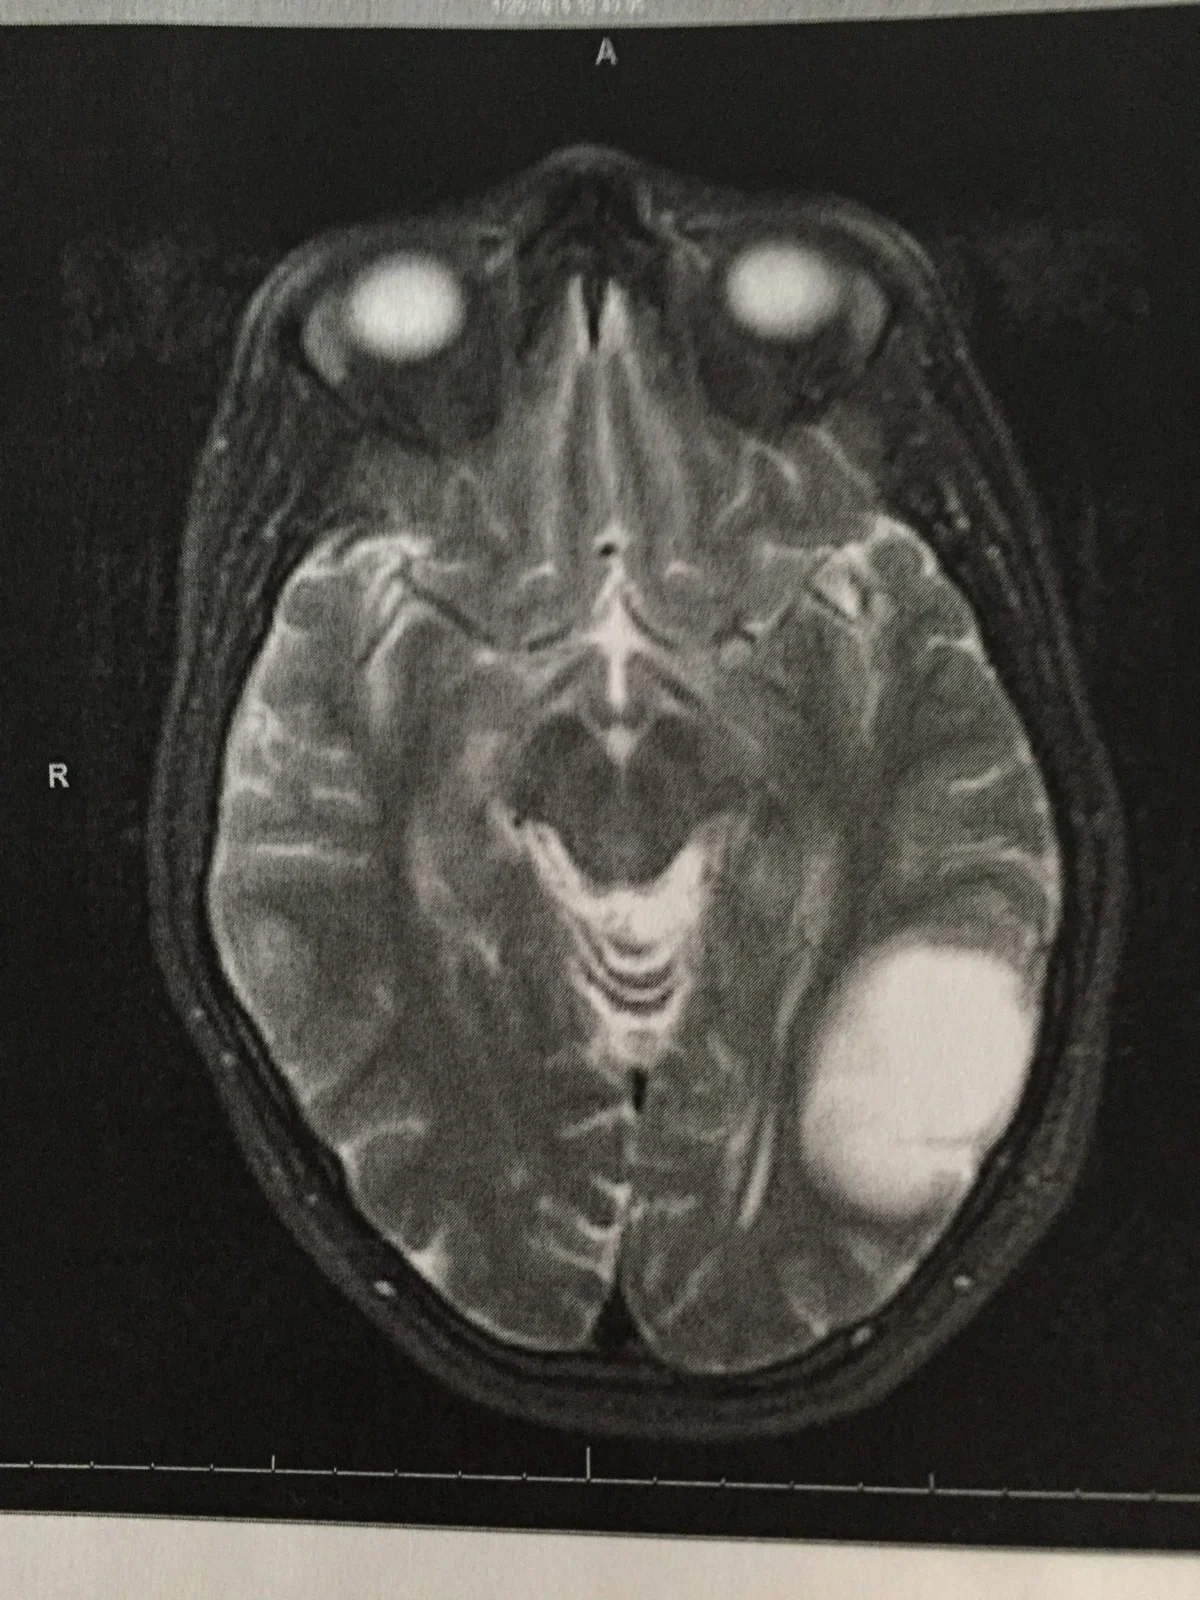

The medical team, recognizing the potential severity of Holly’s symptoms, acted with urgency. She was immediately taken for testing, where the devastating truth was revealed: a tumor had been discovered on the left side of her brain. Within a period that felt both instantaneous and interminable, Holly’s life had dramatically shifted from the joys of new motherhood to the grim prognosis of a Grade 3 anaplastic astrocytoma. The emotional whiplash left her reeling, a state of shock from which it was difficult to emerge.

"When I originally had the diagnosis and saw the tumor, I thought there is no way I can live with this," Holly recounted, her voice still tinged with the memory of that profound despair. "I have a 3-month-old, and I’m never going to see him turn one. I had this precious little baby that I couldn’t nurse anymore, and I couldn’t have any more babies. I had so much going on mentally that I couldn’t even think about anything else." This raw expression of her internal struggle highlights the immense personal toll of the diagnosis, particularly for a new mother whose world revolved around the well-being of her young children. The fear of not being present for their milestones, the inability to fulfill the fundamental nurturing role, and the perceived loss of future family possibilities compounded the medical challenge.